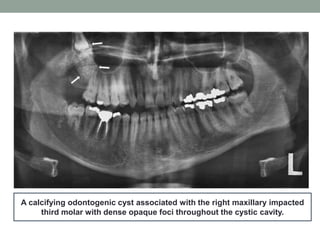

A calcifying odontogenic cyst associated with the right maxillary impacted

third molar with dense opaque foci throughout the cystic cavity.

A calcifying odontogeniccyst associated with the right maxillary impacted third molar with dense opaque foci throughout the cystic cavity.